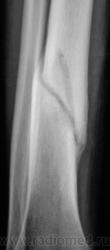

Рановато гипсик сняли, есть угроза повторного перелома.

для 2 мес даже очень хорошо, мес через полтора может уже и наступать

Консолидация хорошая.